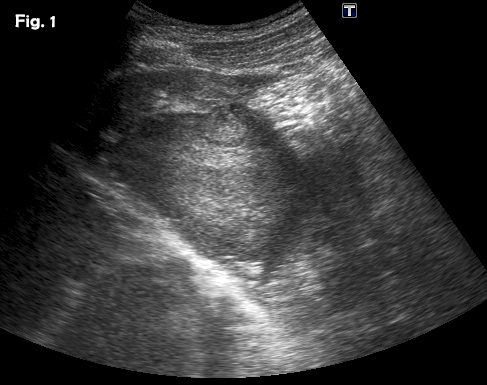

A previously healthy 39-year-old male was referred because of a hepatic mass, found incidentally He was a professional sportsman and regularly participated in competitions. He had taken anabolic steroids for 6-8 weeks two or three times per year from 24 – 32 years old approximately. The remainder of the medical history was unremarkable. Laboratory results showed a slight elevation of ALT and AST with normal bilirubin and alpha-fetoprotein levels. Physical examination was otherwise normal. An abdominal ultrasound showed a well-defined 8.5 x 7.7 cm heterogeneous mass with a hypoechoic peripheral halo in the left lobe of the liver, segments 2 and 3 (Fig 1). A small nodule-in-nodule appearance was evident within the mass as well as some vascularity on colour Doppler. Following the administration of an ultrasound contrast agent (SonoVueTM), the mass showed homogeneous hyper-enhancement in the arterial phase (Fig 2a) (video 1), with wash-out in the late phase in only part of the lesion (video 2), specifically, the nodule-in-nodule appearance area (Fig 2b). These appearances were suggestive of a hepatocellular adenoma with areas of malignant transformation and this was confirmed by both ultrasound guided fine-needle aspiration cytology (video 3) and subsequent histological examination of the surgically resected tumour.

Figure 2:Contrast-enhanced ultrasound (CEUS) in the arterial (a) and late (b) phase. CEUS showed early hyperenhancing features in the arterial phase of the lesion and clear wash out in the small nodule-in-nodule appearance without wash out in the rest of the lesion.

![Hepatic adenoma with focal hepatocellular carcinoma</br> [Aug 2016]](http://s834315022.websitehome.co.uk/wp-content/uploads/2020/11/cotm_august2016_fig02a.jpg)